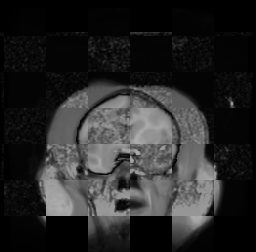

For each of the 10 subjects, we show checkerboard slices in each direction (1) before registration, first row; (2) after rigid->scaleversor->affine registration, second row; and (3) after BSpline registration, third row.

Calvin